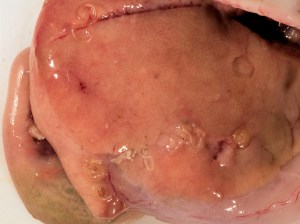

anisakis Y ENDOSCOPIA

El uso de la radiografía y ecografía, puede ayudarnos en el diagnóstico de anisakiasis, pero el diagnóstico de certeza, lo da la visualización de la larva por endoscopia (gastroscopia o más raramente colonoscopia) que además permite en esos casosla extracción de la misma y la resolución de los cuadros agudos. Sin embargo, en la mayoría de los pacientes la anisakiasis es autolimitada, resolviéndose el proceso al expulsar espontáneamente la larva. En algunos casos con complicaciones intestinales (obstrucción, peritonitis,…) puede ser precisa una intervención quirúrgica o tratamiento con corticoesteroides orales.